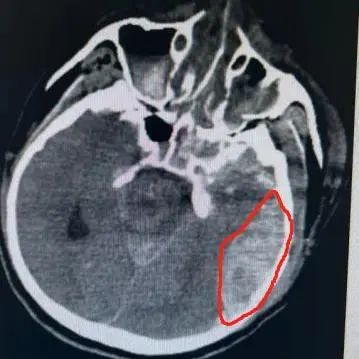

积极抢救后,王先生的血压终于有所上升,立刻为他进行头颅+胸部+全腹部 CT,检查结果显示:他的双侧额骨、颞骨、蝶骨骨折,颅底骨折,颅内积气,左侧颞顶部及右侧顶枕部硬膜下血肿、蛛网膜下腔出血,颈椎 567 锥体横突骨折,右 6-9 肋骨多根多处骨折伴有肺挫伤。

经过 2 个小时紧张的综合抢救后,王先生的血压明显改善,生命体征逐渐稳定,复查头颅 CT,检查结果显示,脑出血明显增多伴有中线偏移,脑疝形成。